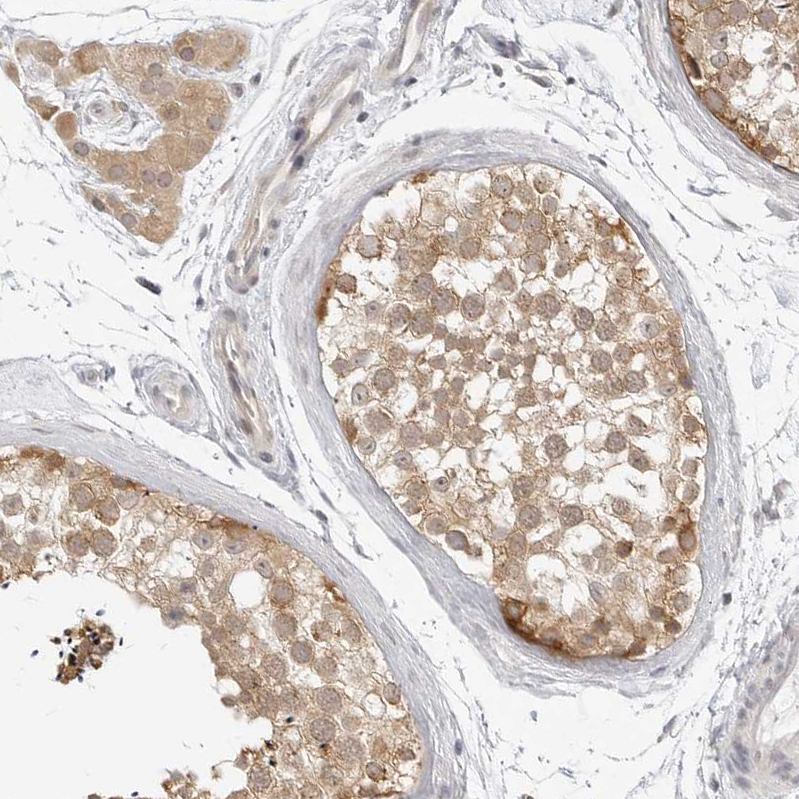

Immunohistochemical staining of human testis shows moderate cytoplasmic positivity in cells in seminiferous ducts and Leydig cells.